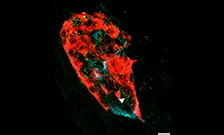

Prof Peter Jones, Dr Chloe Rackham, Dr Sara Caxaria, Miss Ella Hubber - Mesenchymal stromal cells improve the outcomes of islet transplantation in animal models of diabetes. We are investigating the mechanisms through MSCs interact with beta-cells to develop cell-free treatments of islet grafts and of graft recipients. We have recently identified a cocktail of MSC-derived molecules which has beneficial effects on islet function and we are now testing this cocktail in clinically-relevant human islets. We are using single cell RNAseq analysis to identify the effects of MSCs on islet cell gene expression, and we are exploring mitochondrial transfer as a mechanism through which MSCs improve beta cell function.

Using mesenchymal stromal cells to improve the functional survival of islet grafts in type 1 diabetes